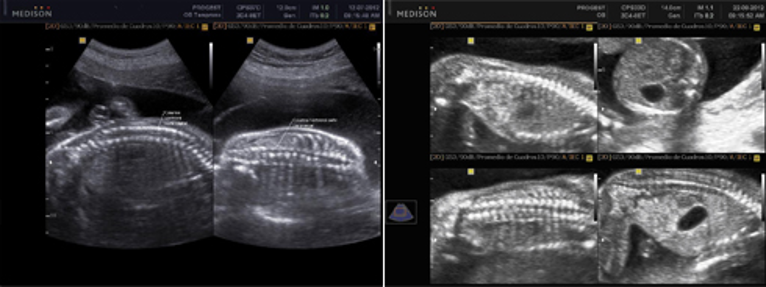

También llamada Ecografía de Tercer Nivel, comprende de un examen detallado de las estructuras anatómicas fetales, así como la valoración del crecimiento y de los marcadores ecográficos de alteraciones cromosómicas del segundo trimestre.

Es la ecografía a nivel obstétrico más importante ya que sirve para diagnosticar y comprobar la existencia de todos los órganos fetales y posibles malformaciones en el feto, y la etapa apropiada para tomarla es de la semana 20 a la 24 de gestación.